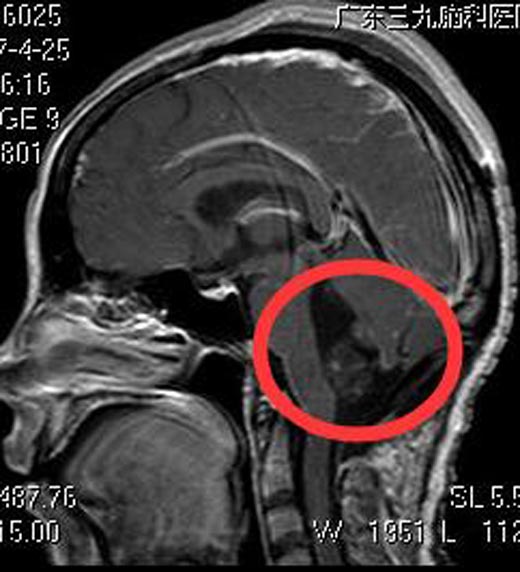

由鲁明主任主刀,在全麻下行四脑室占位切除术,术中显微镜下见皮层下灰黄色肿瘤组织,质软、无包膜,肿瘤分块全切除。术后小娟头晕、行走不稳症状明显好转。术后病理结果提示:脉络丛乳头状瘤 WHO I级。